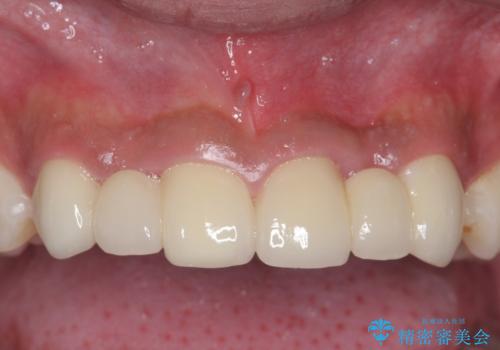

前歯のすきま 生まれつき歯が少ないのを治療

- 前歯の隙間を気にして来院。

生まれつき上の歯が二本少ない状態でした。

バラバラに位置している前歯の位置を矯正治療で修正してからブリッジを装着しています。

矯正治療によって事前に歯の位置を修正しているため、ダミーの歯の大きさも調整し、自然な仕上がりにしました。また、犬歯のねじれを治してから削っているため、神経をとらずに歯の形を整えることができました。